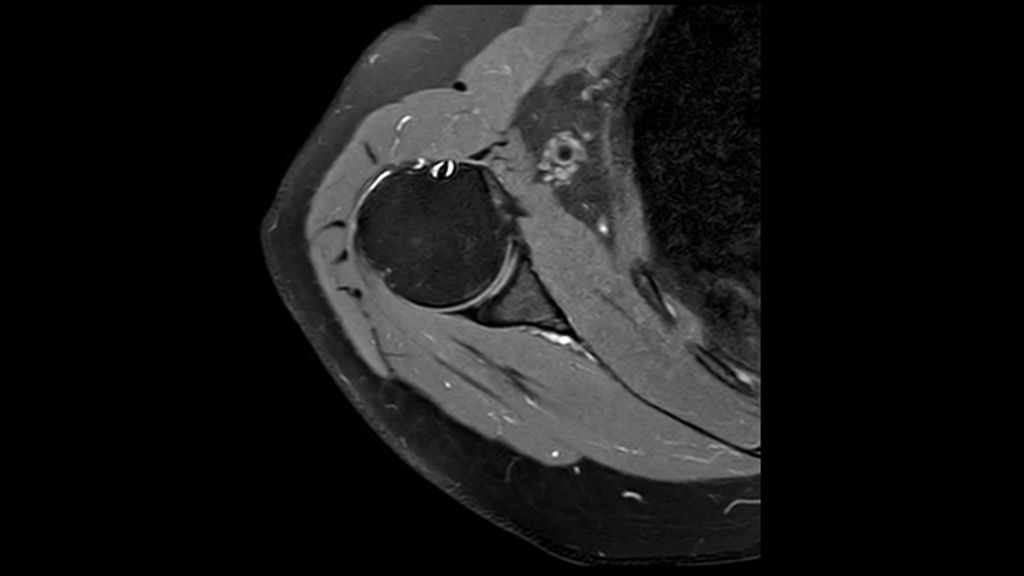

This innovative 1.5T MRI system is powered by Philips exclusive BlueSeal magnet for helium-free operations. And it incorporates a wealth of AI²-driven technologies to simplify and automate the most complex clinical and operational tasks. So you can focus on what matters the most: your patients.

This breakthrough solution is designed to help boost MR productivity, speed up exams, empower clinicians to make informed clinical decisions, and control the costs of MR imaging.